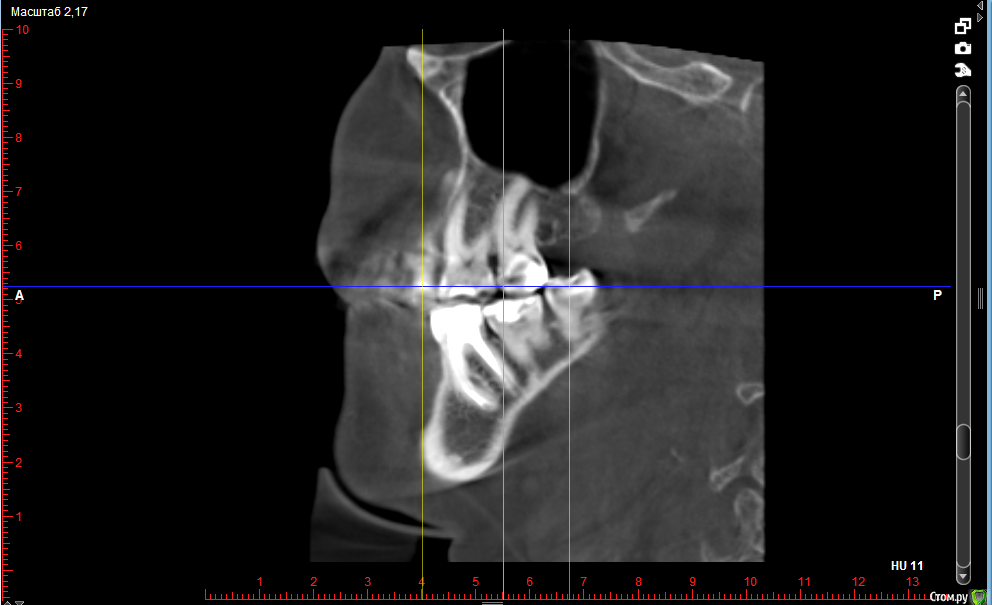

36 - киста зуба (сделала отдельный скриншот)

post-37334-0-03189900-1512417415_thumb.png